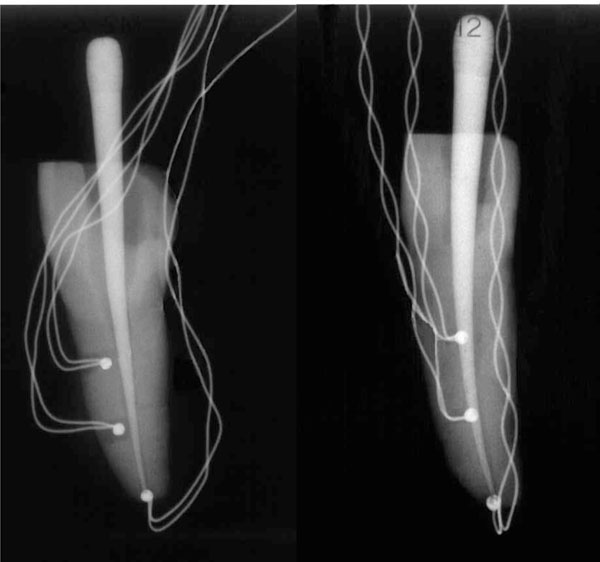

Tracing Sinus Tract With Gutta Percha Point TAKEN WITH XRAY IMAGE YouTube

Tracing Sinus Tract With Gutta Percha Point TAKEN WITH XRAY IMAGE Gutta Percha Through Apex Assuming the operator is right handed, the tweezers holding the accessory point are aligned above the tooth in the right hand, while the left. The company’s roots stem from the desire for product improvements to the items of focus in dr. Deutsch's lectures and daily practice. When in contact with dentine the soluble products of white and grey mta have. Gutta Percha Through Apex.